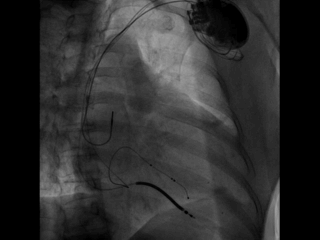

在缝合过程中即由工程师进行无线测试(可不通过程控探头探寻)

如上图,通过Vector Express功能很快自动测试四极多向量的阈值供参考,选择LV2-LV3向量,该向量阈值最低,预估寿命最长

心房、右室、左室的其它参数也均满意

经过术后即可优化,QRS宽度即刻缩窄!预示患者良好的预后。